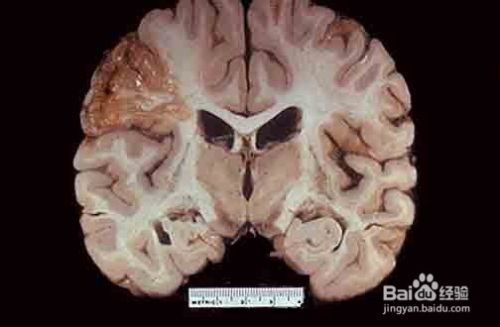

脑萎缩起病较为缓慢,呈进行性加重,多数病人的发病日期难以明确肯定。其临床的表现与脑萎缩发生的部位及程度有关。其中弥漫性大脑皮层萎缩以痴呆、智能减退、记忆障碍、性格改变、行为障碍为主。有的伴有偏瘫和癫痫发作。局灶性脑萎缩以性格改变为主;小脑萎缩以语言障碍及形体的共济失调和震颤为主。从脑萎缩的临床表现来分析,大致又可分为两大类,一是大脑机能衰退,二是痴呆等智能减退。大脑机能的衰退表现为头晕、头痛、失眠、记忆力差、手足发麻、情绪抑郁等;智能减退表现为认知及社会适应能力的障碍,如记忆力、理解力、判断力、计算能力的减退,以至发生痴呆。